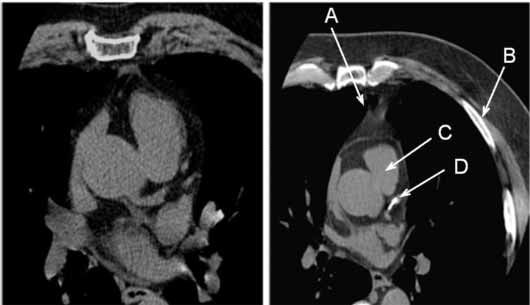

(Izquierda) TC de una arteria coronaria normal.

(Derecha) TC anormal que muestra calcio en la arteria coronaria izquierda.

A: esternón

B: costilla

C: corazón

D: calcio en la arteria coronaria

Nota: Las imágenes se muestra para fines ilustrativos. No trate de sacar conclusiones comparando esta imagen con otras en el sitio. Solamente los radiólogos calificados deben interpretar las imágenes.